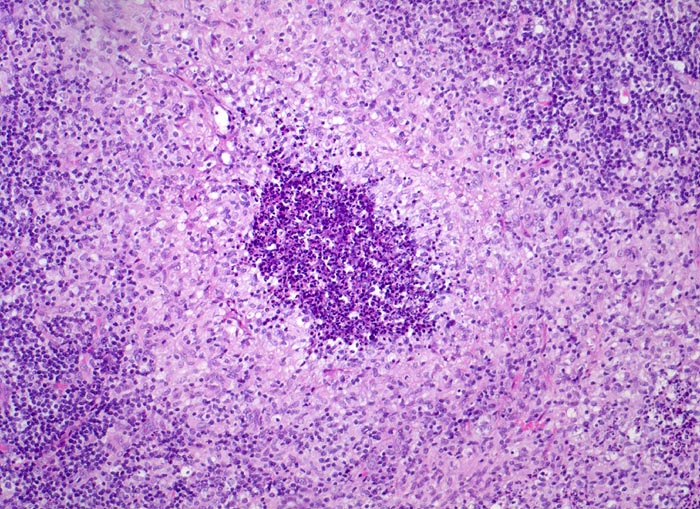

retikulozytär-abszedierende Lymphadenitis bei Katzenkratzkrankheit

Lymphknoten, Axilla

Granulom mit zentraler Nekrosezone mit massenhaft neutrophilen Granulozyten gesäumt von Histiozyten (Retikulumzellen).

Nachweis von kleinen pleomorphen Bakterien

Keine käsige Nekrose wie bei Tbc.